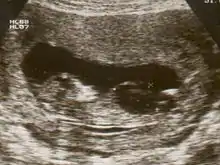

Fetal megacystis[1] is a rare disease that is identified by an abnormally large or distended bladder.

Fetal megacystis is diagnosed during pregnancy by ultrasound imaging procedures. Since it can be associated with genetic abnormalities, further ultrasounds and tests may be administered during pregnancy. It may also be diagnosed as megalocystis, and/or termed megabladder, which is the same condition.